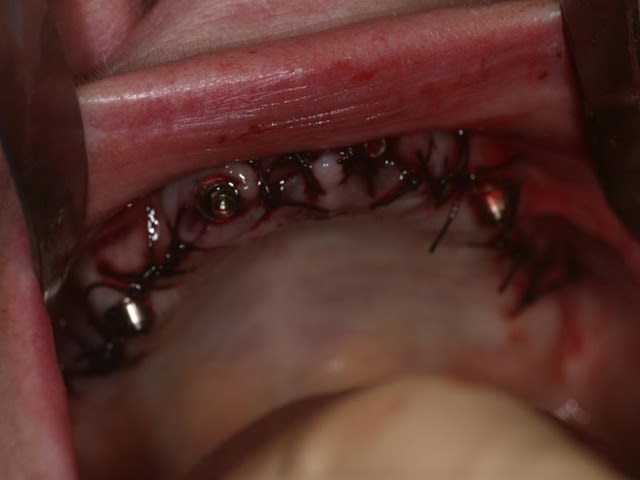

bon, toujours aussi speed je suis, mais après certaines réclamations, et malgrès ma réticence à poser un cas non "consolidé", voici en avant première mon premier all on 4, version photos ratées et non retouchées, mais... speed je suis je vous disais ;)

sto le bla bla, et pasons le diaporama... bon voyage au pays de la mise en charge immédiate totale au maxillaire de fille carole sur dame ginette, une patiente en or que j' adore, et pour qui je suis très très heureuse d' avoir pu réaliser cette chirurgie et la première étape prothétique.....

Elles sont tres bien, tes photos, Carole.

La pose du provisoire est en direct, ou quelques jours plus tard ?